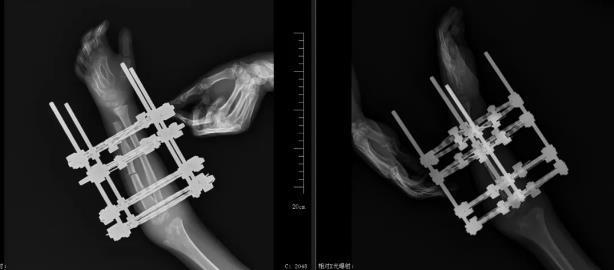

面对这一复杂病例,吴立文医生团队在术前进行了详细的评估和规划。他们通过先进的影像学检查技术,精确测量了患儿前臂骨骼的长度、角度和畸形程度,制定了个性化的手术方案。手术中,团队采用了先进的骨科技术和设备--尺骨截骨+外固定环架技术。这种外固定技术具有良好的力学稳定性,能够同时纠正多平面的复杂畸形,同时避免了传统手术中可能出现的血管、神经损伤等风险。在手术过程中,团队成员各司其职,紧密配合,确保了手术的顺利进行。

术前设计环架的大小与位置

技术突破:微创与导航赋能精准医疗

为降低手术创伤,团队采用微创的方式,结合术中透视系统,牢牢把控截骨的位置及固定的角度。吴立文医生指出:“这是患儿的第一次手术,我们这次先将环形架子固定好,并将下段尺骨与桡骨锁定,这样在做尺骨延长以后会将桡骨头向下复位;待桡骨头复位满意后,将下段尺桡骨解锁,上段尺桡骨固定,这样继续延长尺骨将尺骨延长至正常水平,架子就可以取出来了。”

手术成功完成,外固定满意

术后X线:尺骨已截骨,外固定牢固